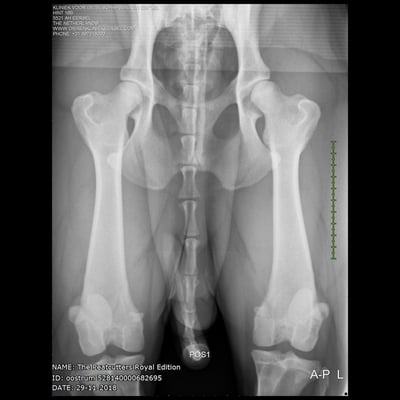

HD: C

ED: 0/0

pennhip: 0.38/0.39

Sjors his official hip and elbow results with the photos. X-rayed at 20 months of age. HD-C, ED-0.